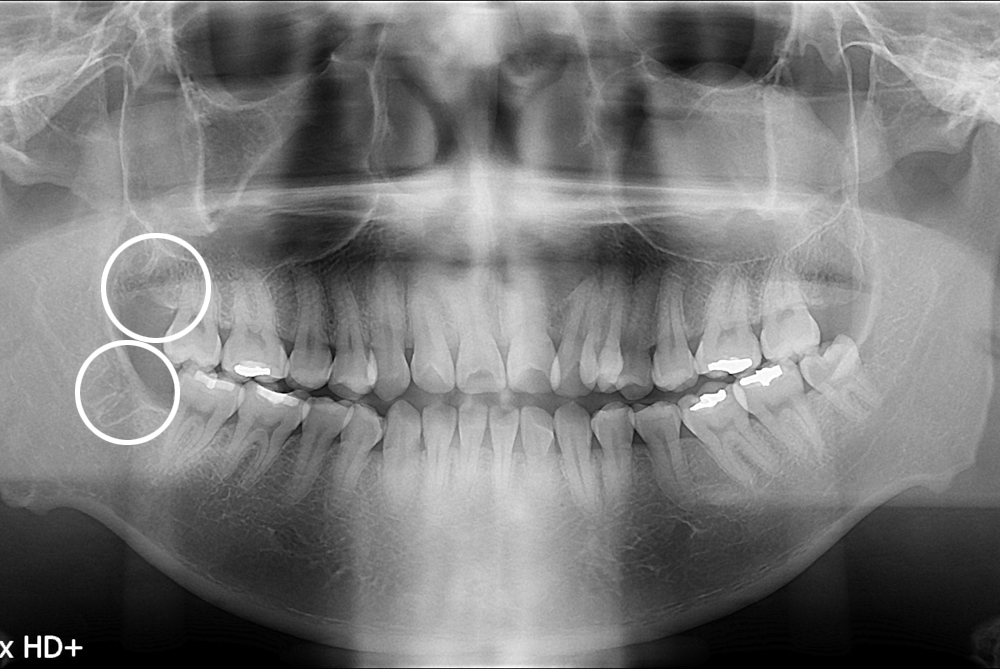

[사랑니] 난발치 사랑니 발치

치료전 : 2017-06-16